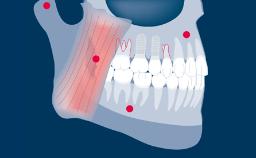

Existem muitas opções convencionais de tratamento fixo que podem ser consideradas para a substituição de dentes ausentes. Incluindo Próteses Dentárias Fixas ou PDFs, PDFs com cantilever e PDFs adesivas. A escolha da opção de tratamento deve levar em conta os desejos do paciente e as necessidades percebidas. O tratamento deve ser guiado pelo planejamento da prótese. Quando mais de uma opção prostética é possível, os resultados do tratamento publicados na literatura científica devem ser considerados e usados como um fator para aconselhar o paciente sobre a opção mais adequada. Este módulo discutirá as vantagens e desvantagens das opções convencionais de tratamento fixo para substituir os dentes ausentes e comparar os resultados e as indicações de tratamento publicados com as de próteses fixas implantossuportadas.